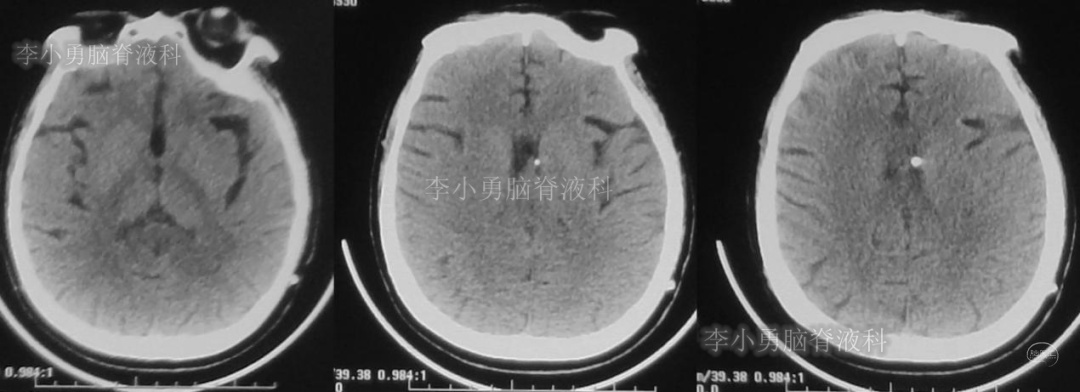

患者于2018年1月29日,突发头痛、头晕、恶心、呕吐,并高热40度。在当地医院门诊输入4天抗生素后发热缓解,但出现了双眼不能上视(眼球不能向上看)。5天后即2018年2月3日,在当地的第1家医院:浙江省海宁市某医院行头颅CT(图-1)发现脑室扩张,当地医院诊断为“梗阻性脑积水”。

图-1:2018年2月3日头颅CT